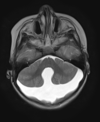

Q

A

Esclerose mesial temporal

Observe a perda de volume, que indica atrofia e causa aumento secundário do corno temporal do ventrículo lateral.

O sinal alto no hipocampo reflete a gliose.